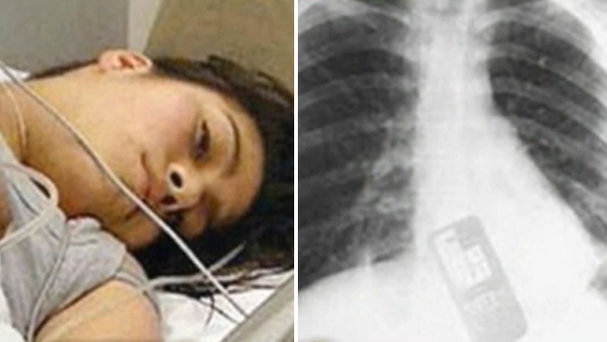

Se tragó celular para que no leyeran los mensajes

Una brasileña de 19 años, que discutía con su novio que quería leer los mensajes de su celular,no encontró mejor formar de terminar la pelea que tragándose el teléfono.¿Qué se imaginan que puede estar escondiendo?

Afortunadamente Adriana Andrade fue trasladada a un hospital donde la atendieron a tiempo para evitar que la cosa se pusiera más color de hormiga que lo que ya estaba…. Claro que después de ver su reacción, tanto su novio como los médicos, familiares y amigos, están en plan de averiguar qué hay en ese teléfono, así como para haber tomado tan loca y drástica decisión.

Respecto a su salud, la chica se encuentra estable y será dada de alta pronto, pero está clarito que su novio, le va a pedir explicaciones respecto de los mensajes que trató de ocultar.